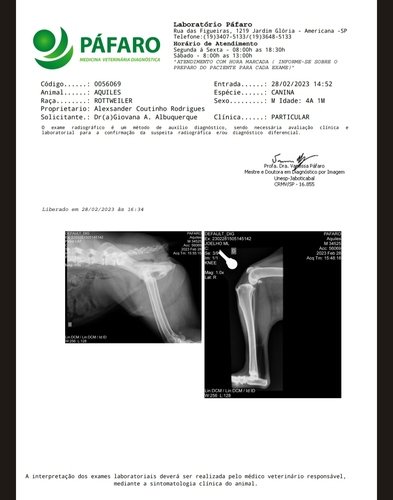

Meu papai logo me socorreu e me levou ao medico veterinário, me medicaram e cuidaram muito bem de mim como sempre fazem. Mas depois disso não fui mais o mesmo fui perdendo o movimento da minha perninha direita, meu papai vem fazendo de tudo para me ajudar e cuidar de mim. Faz meses que venho emagrecendo muito, pois não consigo comer pois sinto muita dor na minha perna e quadril. Meu papai me levou para fazer exames mais profundos e não teve boas notícias, DESCOBRIRAM QUE ESTOU COM DISPLASIA COXOFEMORAL, E RECENTEMENTE FUI DIAGNOSTICADO COM UM POSSÍVEL CÂNCER . Sinto muita dor, perdi muito Peso 16kilos estou muito triste e cansado. Descobri que se eu deitar encostado com as perninhas na parede amenizo minha dor. Por favor me ajude a voltar distribuir amor. Descobriram que não posso mais fazer cirurgia para cuidar da minha displasia, pois possivelmente um câncer está se desenvolvendo e tenho que fazer quimioterapia e tratamentos . Obrigado por nos ajudar quer ver meus exames e minha situação siga o perfil do meu papai lá no Instagram @alexsanderrcoutinho